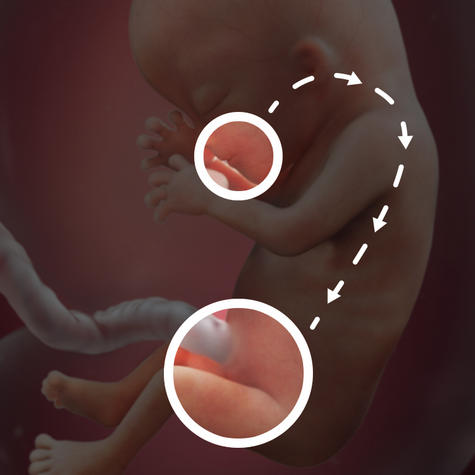

Ваша дитина починає ковтати і мочитися амніотичної рідиною

Голова вашої дитини стає більш пропорційною, її розмір становить приблизно третину від розміру тіла

У вашої дитини з'являються його власні, унікальні відбитки пальців

На 13 тижні плід розвивається дуже швидко, буквально по годинах. Його вага вже досягає в середньому 15-20 г, розмір - 8 см. У нього вже повністю сформовані найважливіші системи організму, є пальці і навіть нігті. Плід все більше зовні стає схожий на людину, його голова вже не така велика по відношенню до тіла, а руки досягають такої довжини, при якій він легко дотягується ними до рота.

Дитина на 13 тижні внутрішньоутробного розвитку здатний відчувати смаки і запахи. Звичайно, це він робить ще неусвідомлено, на рівні вроджених інстинктів. Відомо, що саме в цей період часу у майбутнього людини закладаються смакові переваги. Плід реагує на їжу, яку вживає його мама. Він уже має майже сформованим кишечником.

Риси обличчя ще не сформовані, проте на даному етапі розвитку у дитини вже відзначаються індивідуальні особливості: будова підборіддя і носа, розріз очей і т.д.